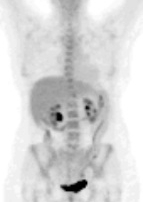

Biologie hémogramme hémoglobine 10,8 g/dl, LDH 180% la valeur normale. Bilan hépatique normal.

Gastroscopie et écho-endoscopie digestive : estomac normal. Adénopathies coeliaques confluentes, pancréas normal.

Biopsie d’une adénopathie sus-claviculaire conduit au diagnostic de lymphome diffus à grandes cellules B CD20+, CD5-, CD10-, BCL6+, BCL2 faible. Biopsie médullaire normale.

Classement LNH diffus à grandes cellules B CD20+, stade III, OMS = 1, LDH augmentées soit 2 facteurs selon IPIaa.

Décision : R-CHOP21 x 8 cycles avec prophylaxie neuro-méningée par 4 PL méthotrexate, en raison de l’IPIaa à 2 et des LDH augmentée. Evaluation par scanner après 4 cycles et par TEP-FDG après 8 cycles.

Classement rémission complète avec adénomégalies résiduelles sous- diaphragmatiques non hypermétaboliques

Décision surveillance.